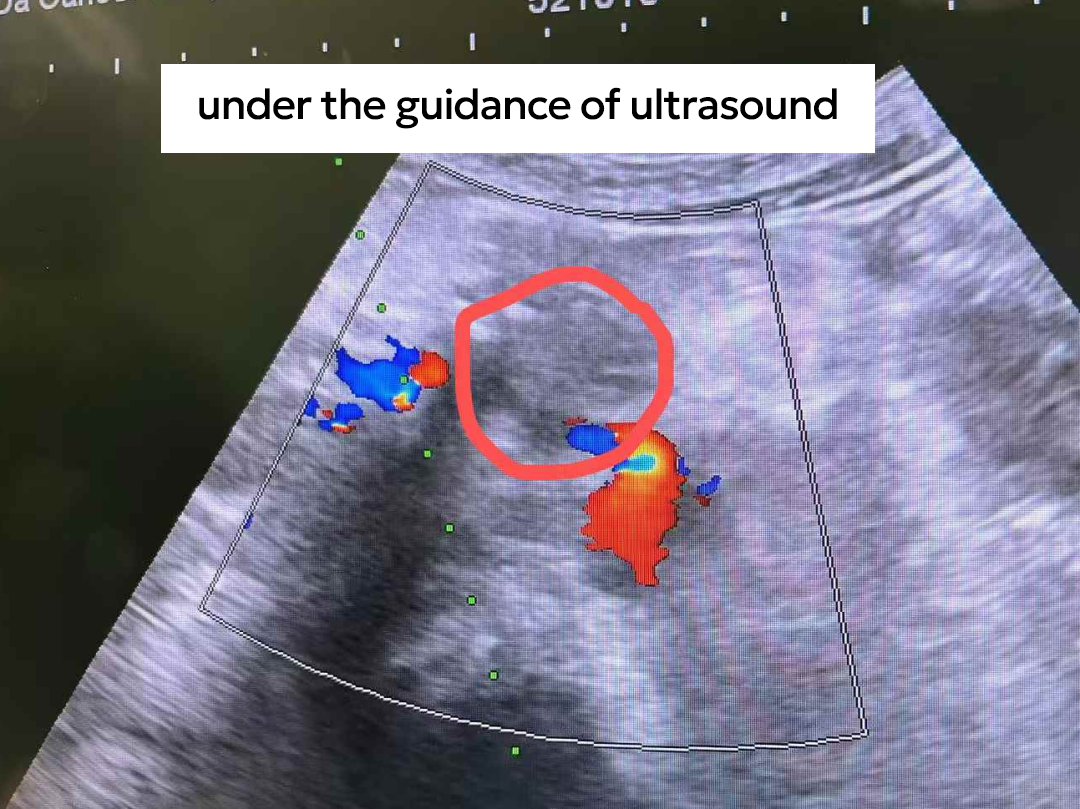

Maureen (pseudonym), from Kenya, began experiencing abdominal discomfort in February last year. Local doctors initially suspected a Helicobacter pylori infection. However, after a period of anti-infective treatment, her pain did not improve. Sensing something was wrong, she underwent further examinations, and an ultrasound revealed a mass in the pancreas.

Examinations revealed that her pancreatic cancer was already at Stage III, with secondary malignant retroperitoneal lymph node involvement, making curative surgery impossible. Dr. Pang Xiaoming explained her condition clearly in plain language, patiently listening to her needs to tailor a more suitable treatment plan.

After multidisciplinary consultation, the team performed NanoKnife ablation of the pancreatic tumor combined with celiac plexus neurolysis. Postoperatively, immunotherapy was administered to control the tumor while alleviating cancer-related pain.